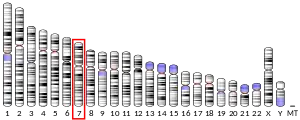

.png.webp)

In mammals, the genome only contains one gene for tropoelastin, called ELN. The human ELN gene is a 45 kb segment on chromosome 7, and has 34 exons interrupted by almost 700 introns, with the first exon being a signal peptide assigning its extracellular localization. The large number of introns suggests that genetic recombination may contribute to the instability of the gene, leading to diseases such as SVAS. The expression of tropoelastin mRNA is highly regulated under at least eight different transcription start sites.

Tissue specific variants of elastin are produced by alternative splicing of the tropoelastin gene. There are at least 11 known human tropoelastin isoforms. these isoforms are under developmental regulation, however there are minimal differences among tissues at the same developmental stage.[9]